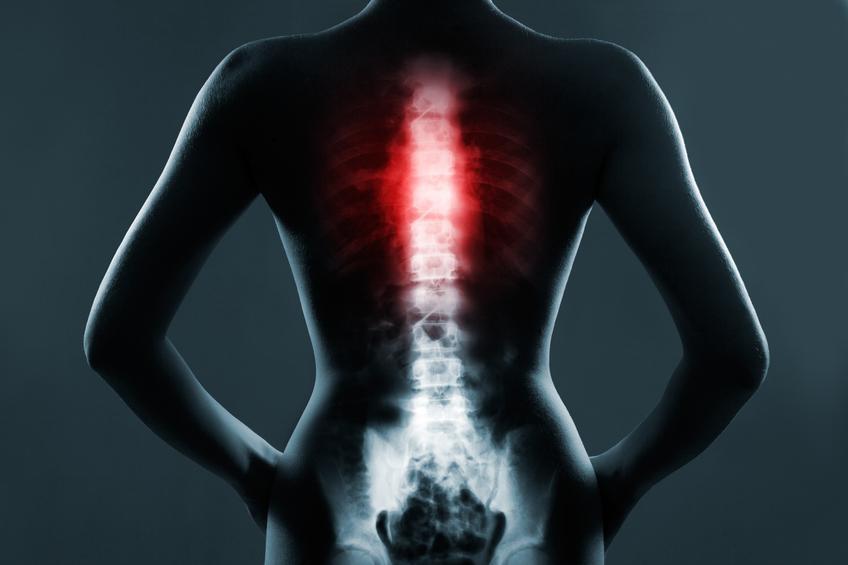

As vértebras torácicas

São as vértebras com menor mobilidade e maiores que há, encontram-se na continuação das cervicais, que se ligam com a cabeça, e antes dos lombares, se unem com a pélvis e as extremidades inferiores. Portanto, estas 12 vértebras torácicas ou dorsais estão na parte média da coluna vertebral e se unem às costelas graças à sua articulação. Denominam-se com um T à frente que indica que pertencem à região torácica, por isso encontramos as vértebras desde o T1 até ao T12.

Quais são os ossos do tórax - Os ossos da caixa torácica